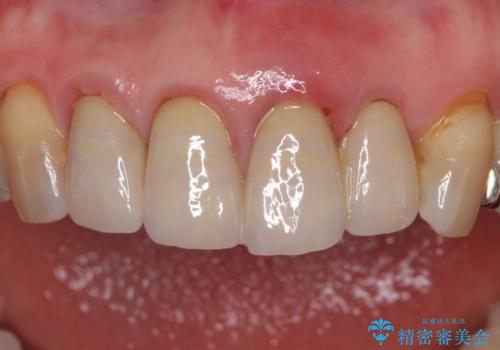

1. 折れてしまった前歯 インプラントによる補綴治療の治療前

3. 折れてしまった前歯 インプラントによる補綴治療の治療後